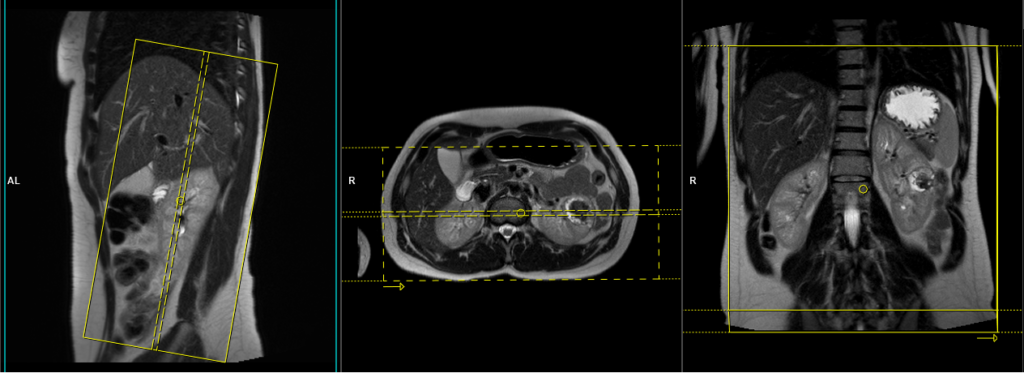

T2 HASTE\t2 tse coronal 4mm

Plan the coronal slices on the axial plane and angle the positioning block parallel to the right and left kidneys. Check the positioning block in the other two planes. Provide an appropriate angle in the sagittal plane (parallel to the long axis of the kidney). Ensure that the slices are sufficient to cover both kidneys from anterior to posterior. Phase oversampling must be used to avoid wrap-around artifacts. Instruct the patient to hold their breath during image acquisition. (In our department, we instruct patients to take two breaths in and out before giving the instruction to ‘breathe in and hold’.)